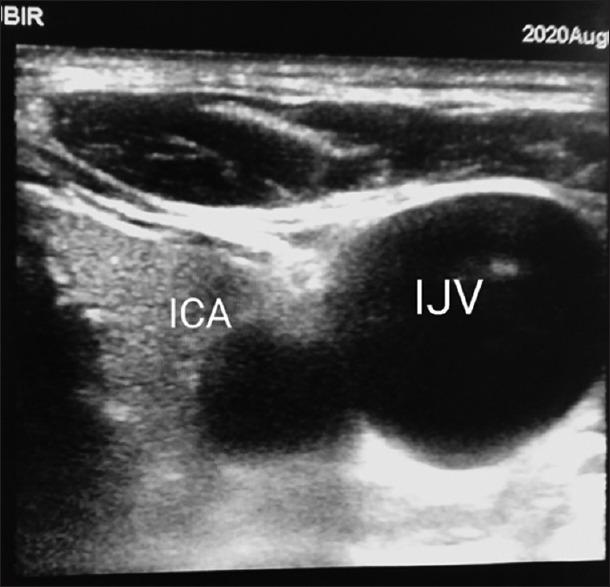

After the detection of novel coronavirus (2019) as the cause of a cluster of pneumonia in Wuhan, China, at the end of 2019, more than 10 million confirmed cases of coronavirus disease 2019 (COVID-19) have been reported around the globe. In the COVID-19 intensive care unit (ICU), the use of stethoscope is minimal for obvious reasons. Shifting of COVID-19 patients out of ICU setup increases the risk of transmission of infection to health-care workers as well as jeopardizes the safety of patients. Hence, diagnostic imaging has emerged as a fundamental component of the current management of COVID-19. Lung ultrasound (LUS) imaging has become a safe bedside imaging alternative that does not expose the patient to radiation and minimizes the risk of contamination. Ultrasound (USG) can be used to scan almost all vital organs (heart, kidney, vascular, brain, etc.) and also help in rapid decision-making regarding the management of COVID-19 patients. In this note, we review the current state of the art of LUS in evaluating pulmonary changes induced by COVID-19. The goal is to identify characteristic sonographic findings most suited for the diagnosis of COVID-19 pneumonia infections as well as to assess the impact of infection on other organs and utilizing the same in the management of COVID patients without compromising on the safety of patient or health-care provider.

2019年末在中国武汉发现新型冠状病毒(2019)是一组肺炎病例的病因后,全球已报告超过1000万例2019冠状病毒病(COVID-19)确诊病例。在COVID-19重症监护病房(ICU),由于显而易见的原因,听诊器的使用极少。将COVID-19患者转出ICU会增加感染传播给医护人员的风险,同时也危及患者安全。因此,诊断成像已成为当前COVID-19管理的一个基本组成部分。肺部超声(LUS)成像已成为一种安全的床旁成像选择,不会使患者暴露于辐射下,并将污染风险降至最低。超声(USG)可用于扫描几乎所有重要器官(心脏、肾脏、血管、大脑等),也有助于对COVID-19患者的管理做出快速决策。在本笔记中,我们回顾了LUS在评估COVID-19引起的肺部变化方面的当前技术水平。目标是确定最适合诊断COVID-19肺炎感染的特征性超声表现,以及评估感染对其他器官的影响,并在不损害患者或医护人员安全的情况下将其用于COVID患者的管理。